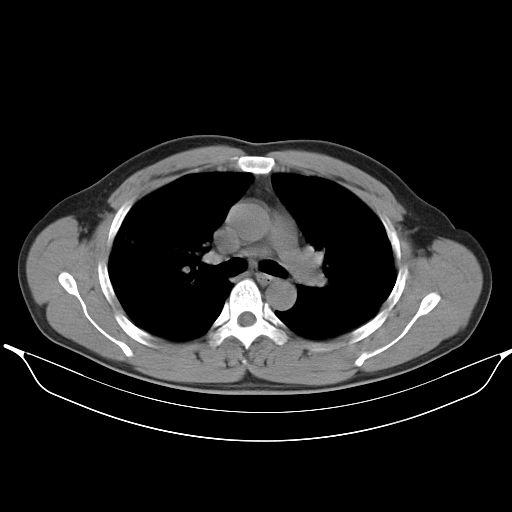

标题: CT25490:男,40岁,体检发现;无其它不适。 [打印本页]

标题: CT25490:男,40岁,体检发现;无其它不适。

考虑右下肺周围性肺癌并肺内多发转移,纵隔淋巴结转移!

支持 !考虑右下肺周围性肺癌并肺内多发转移,纵隔淋巴结转移,(气管前腔静脉后,隆突下,主动脉弓下都有了)

考虑肺霉菌病。

考虑:1、过各敏性肺炎可能性大,建议定期复查。